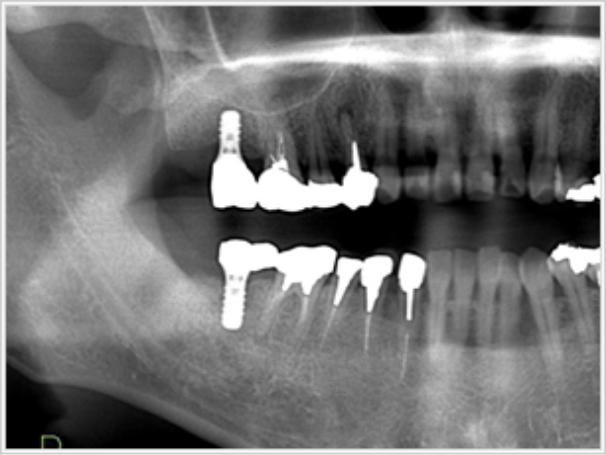

右上奥歯部分欠損

- 治療内容

- 右上奥が歯周病でグラグラしていたので、抜歯後インプラント治療が決定。

しかし骨が薄いため、サイナスリフト治療を開始。骨を足すこと同時にインプラントを入れております。

インプラントはストローマン。

- 治療期間

- 7ヶ月間(インプラント入れてから完成まで)

奥歯(セラミック2本)

80万円(税込)

+サイナスリフト

10万円(税込)